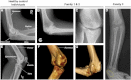

The study of homeotic-transformation mutants in model organisms such as Drosophila revolutionized the field of developmental biology, but how these mutants relate to human developmental defects remains to be elucidated. Here, we show that Liebenberg syndrome, an autosomal-dominant upper-limb malformation, shows features of a homeotic limb transformation in which the arms have acquired morphological characteristics of a leg. Using high-resolution array comparative genomic hybridization and paired-end whole-genome sequencing, we identified two deletions and a translocation 5' of PITX1. The structural changes are likely to remove active PITX1 forelimb suppressor and/or insulator elements and thereby move active enhancer elements in the vicinity of the PITX1 regulatory landscape VSports手机版. We generated transgenic mice in which PITX1 was misexpressed under the control of a nearby enhancer and were able to recapitulate the Liebenberg phenotype. .